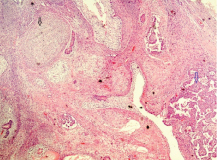

Testicular neoplasm of germ cell origin, constitute more than 95% of these tumours and it is the most common malignancy in men aged between 18-35 years [23]. We found 27 cases (73%) of germ cell testicular tumours with a mean age of 32.4 years. Out of these germ cell tumours, 13 cases (48.2%) were of seminomas with mean age of 37.9 years and 14 cases (51.8%) of non-seminomatous tumours with mean age of 27.5 years. This confirms the known younger age of patients with non-seminomatous tumours compared to seminomatous subtype [16,24,25]. Gross examination of seminomas, showed a well defined, creamish yellow homogenous firm mass, ranging from 4 to 10 cm. Microscopic examination revealed monotonous cell population divided into lobules by thin fibrovascular stroma [Table/Fig-5,6].

Gross photograph of seminoma showing a well defined, yellow homogenous testicular mass.

High power view showing monotonous tumour cells divided by thin fibrovascular septae (H & E- 400x).